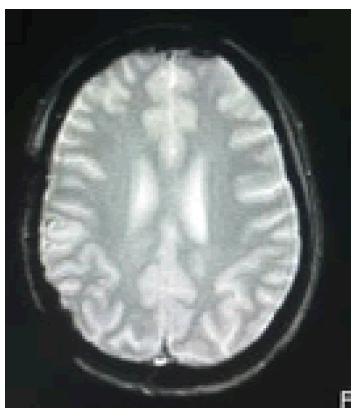

Basic laboratory examinations including CBC, Sodium, Potassium, creatinine, coagulations studies (PT, aPTT), urinalysis, 12L ECG and Chest x-ray were done and all revealed unremarkable results. Having been unsuccessfully treated as a case of migraine type headache, a cranial MRI with gadolinium contrast done revealed a 4.1 × 2.8 × 3.8 cm heterogeneously enhancing right parietal extra axial mass along with crescentic subdural lesion at the right frontotemporoparietal area, measuring approximately 0.9 cm in widest diameter with a midline shift of 1.2 cm, associated with focal areas of necrosis, as well as intralesional blooming dark signals that likely represented blood products exhibiting mass effect and surrounding perilesional vasogenic edema (Figures 1 and 2).

Figure 1: (T1+C) Large, avidly enhancing extraaxial mass ms. 4.1 x 2.8 x 3.8 cm at the right parietal region. (Pre-operative MRI).

Figure 2: (GRE) crescentic extraaxial blooming dark subdural fluid collection signal at right frontotempo-parietal (Pre-operative MRI).